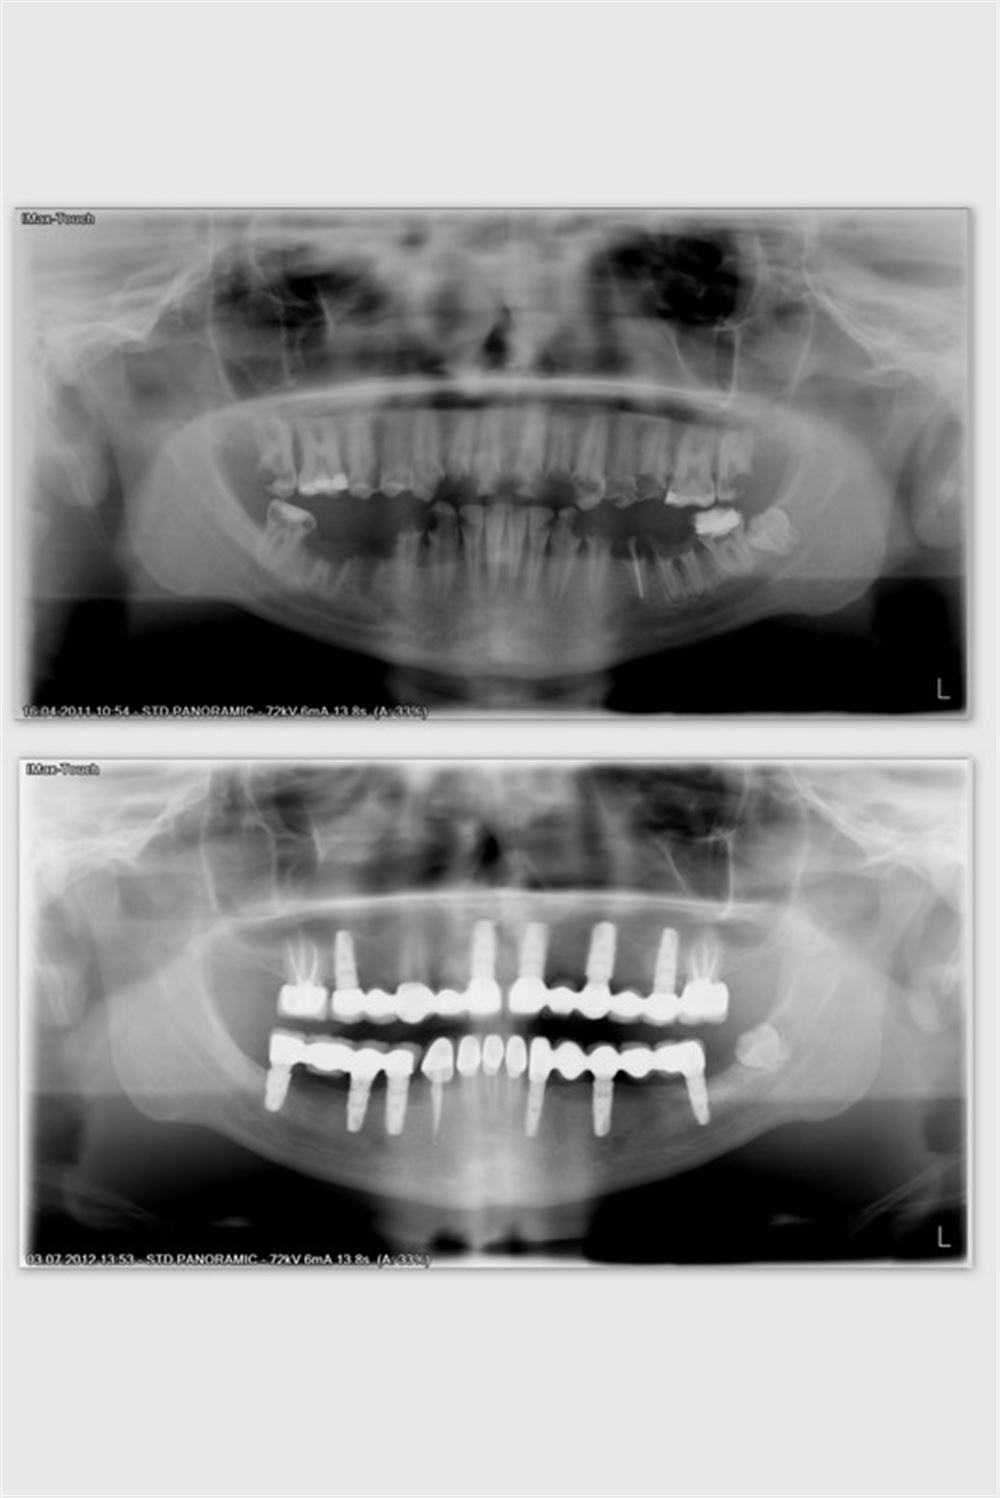

depigmentasyon+gingivektomi+implantx8+Implant supported porcelain fused to metal crown (28 units)

before&after